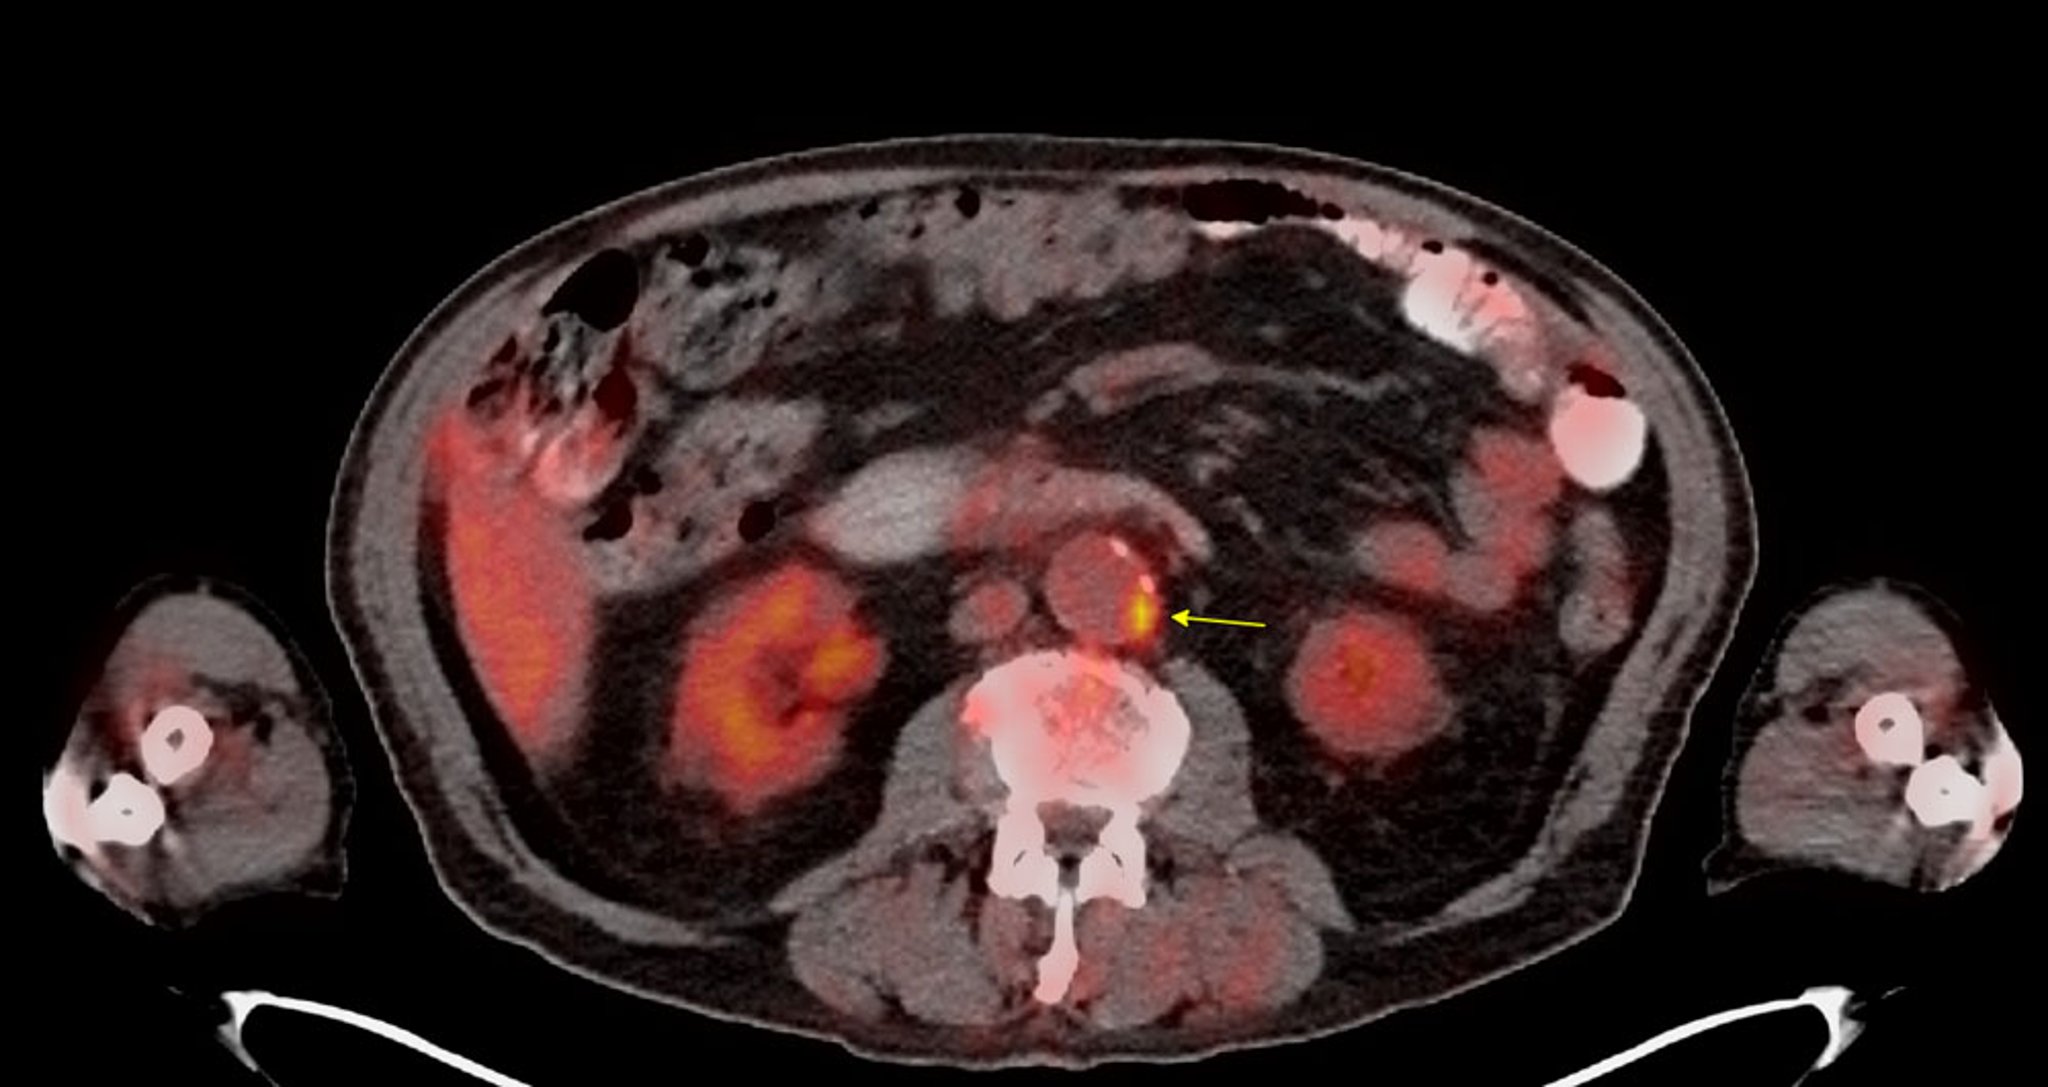

氟-18标记脱氧葡萄糖(FDG)/正电子发射断层扫描(PET)

此FDG-PET扫描显示肾下腹主动脉存在一个高代谢活性的动脉粥样硬化斑块(箭头所示)。

Image courtesy of Attila Feher, MD, PhD.